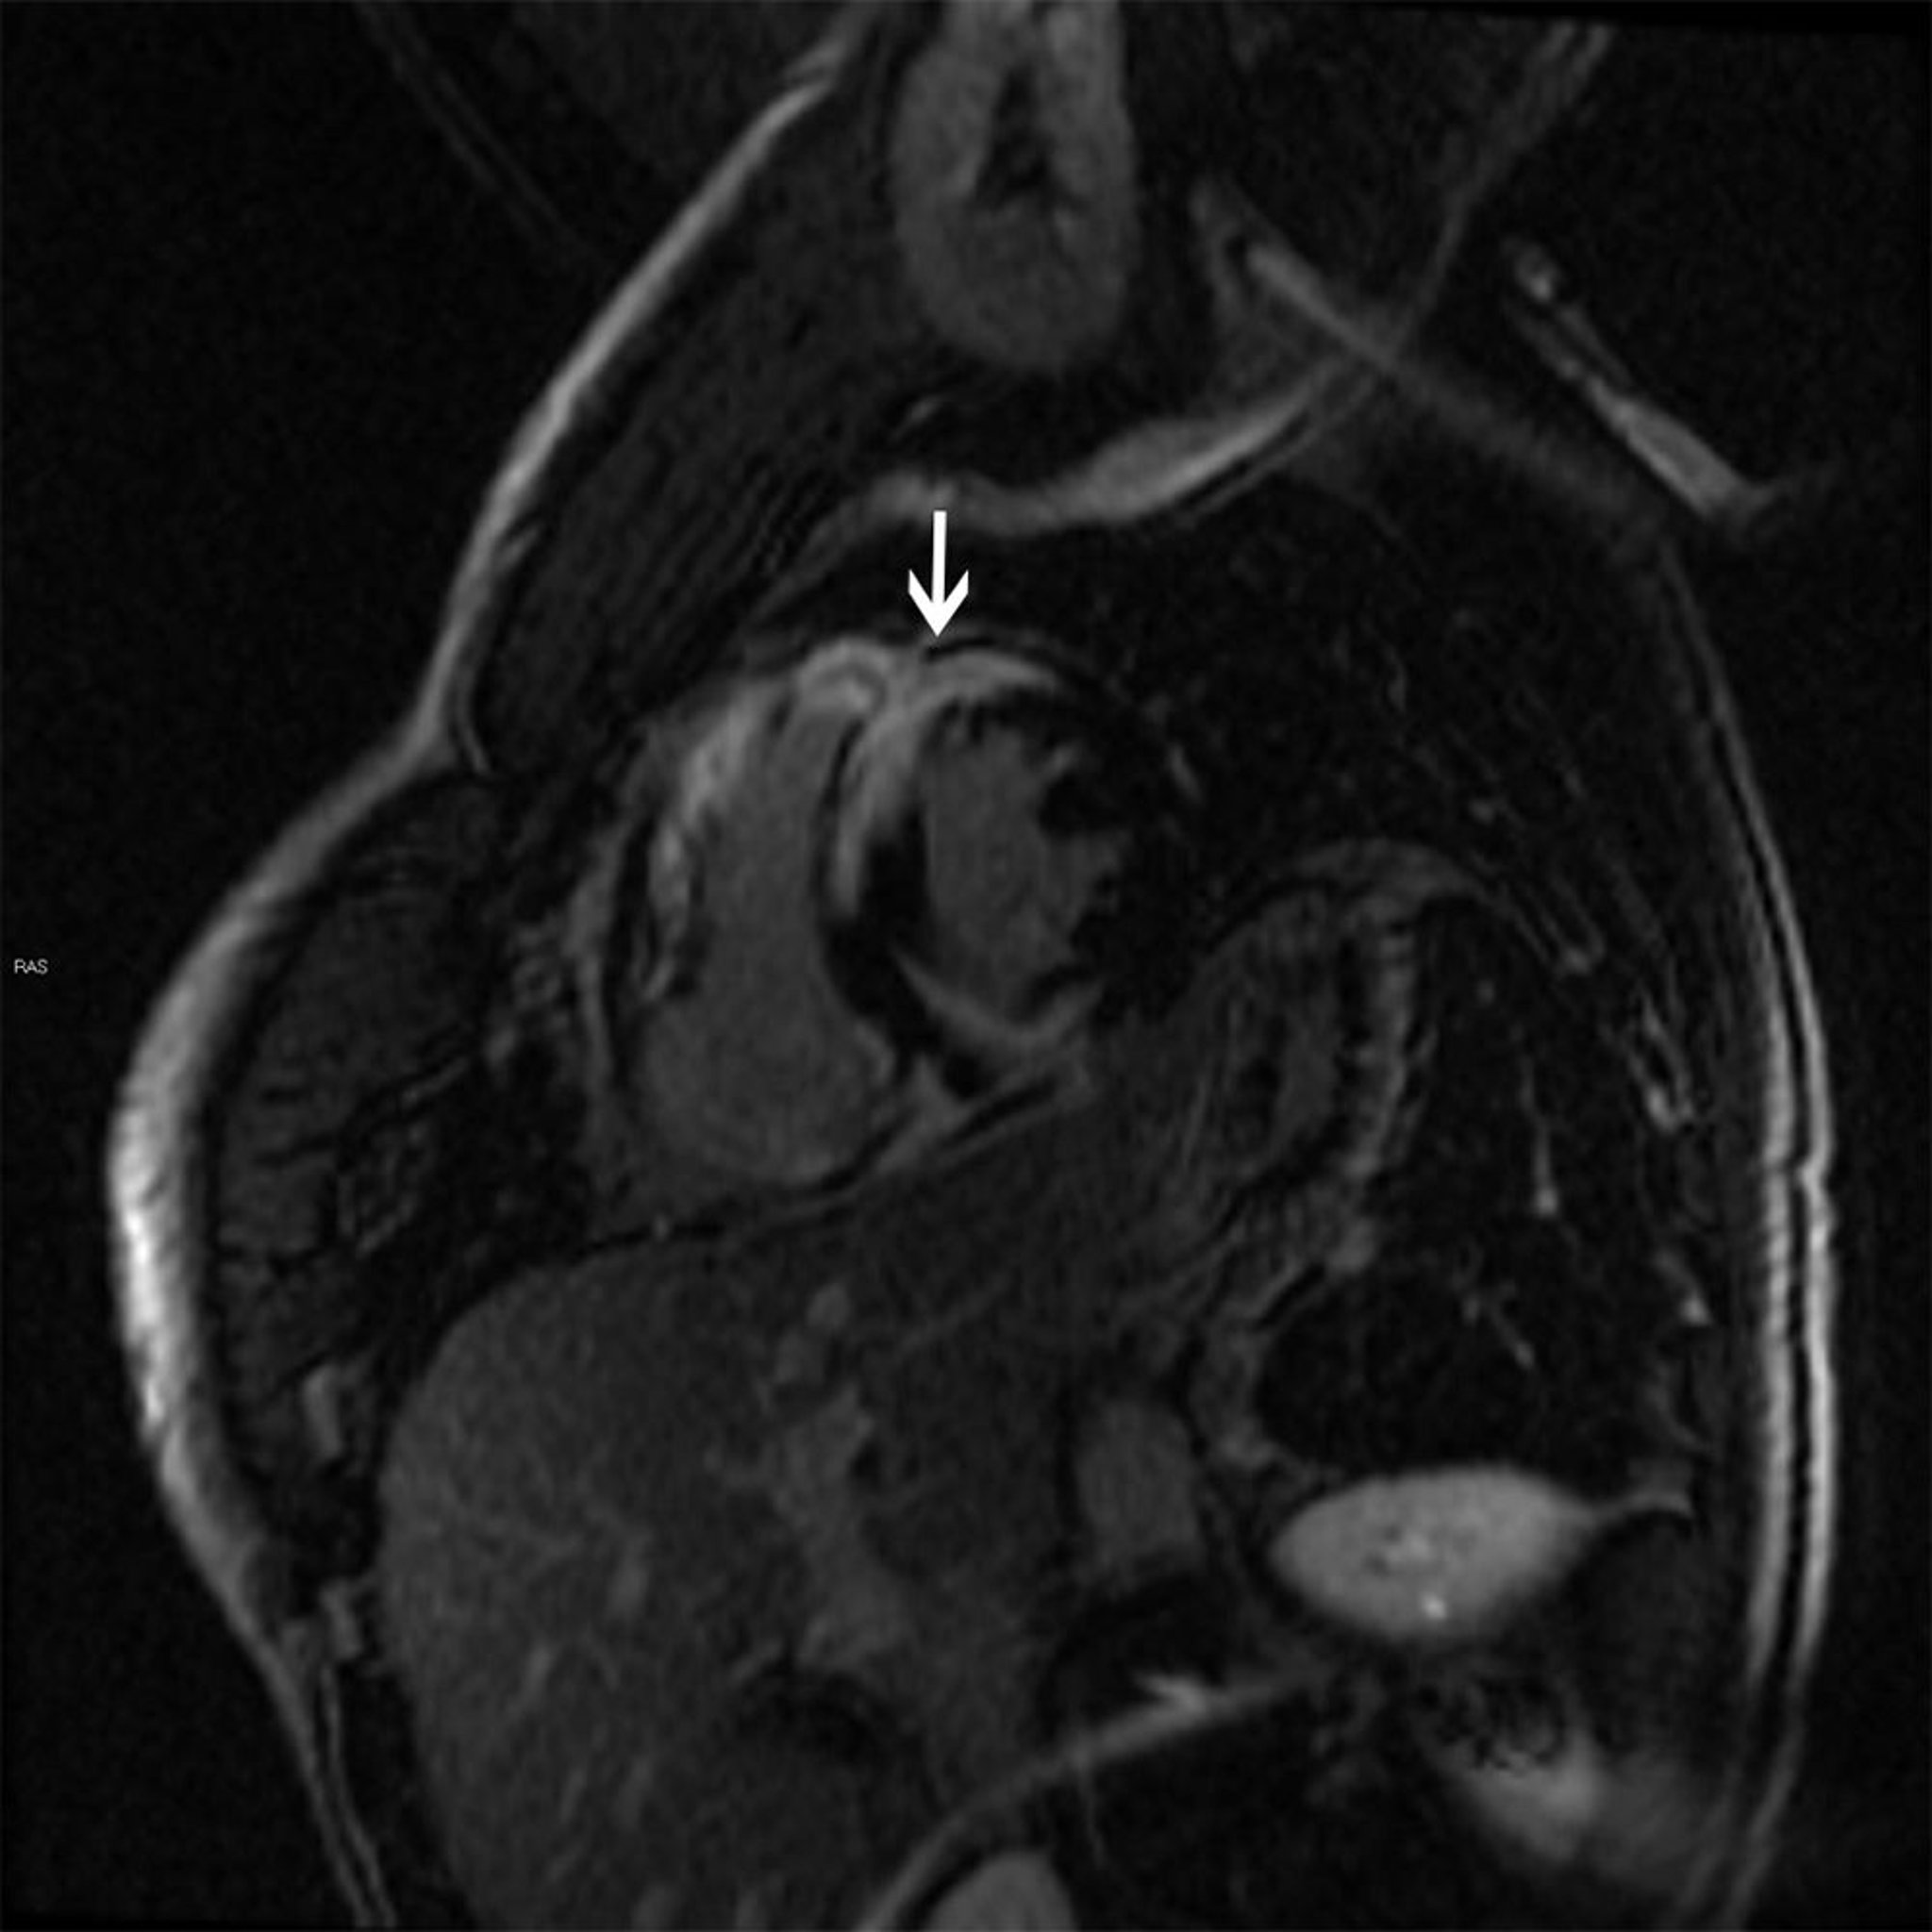

Signes IRM de sarcoïdose cardiaque

Cette IRM cardiaque montre un motif de rehaussement transmural tardif (flèche) au gadolinium caractéristique de la sarcoïdose qui peut provoquer une cardiomyopathie dilatée ou hypertrophique.